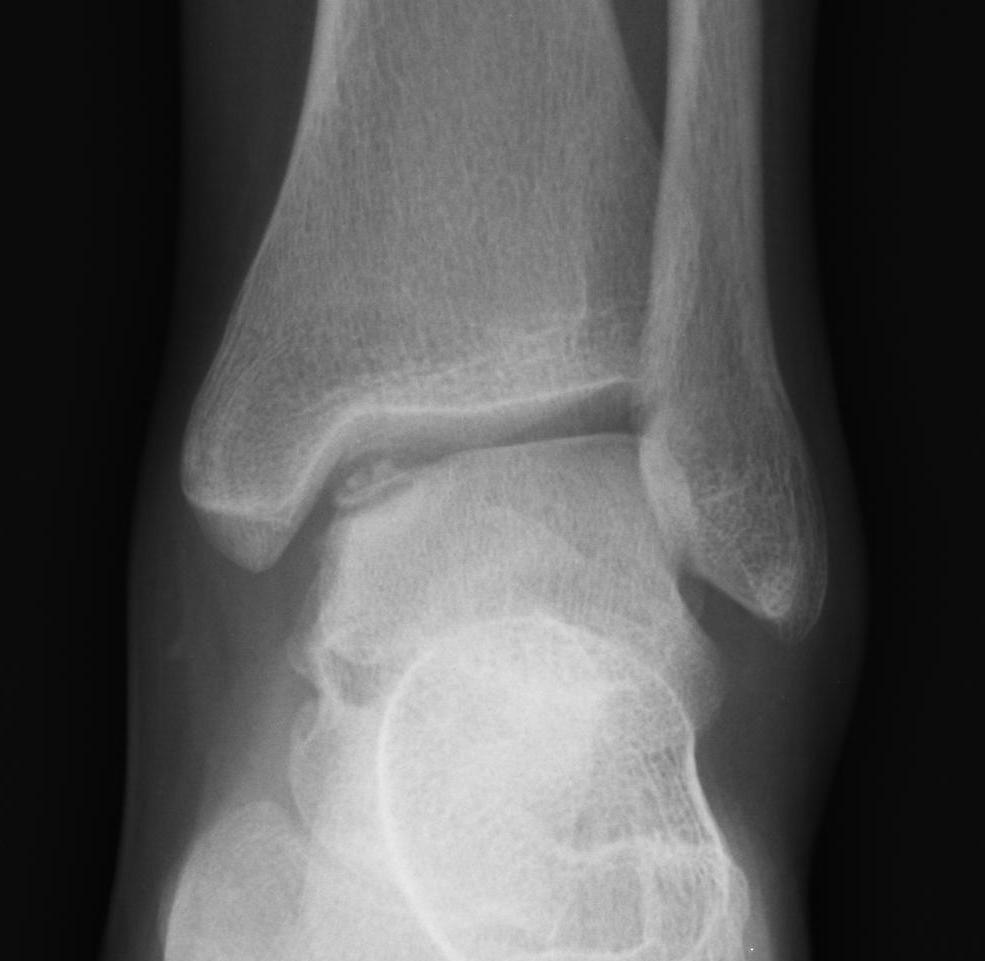

Xray

Stage II medial osteochondral fragments

Stage III medial osteochondral fragments

Stage IV anterolateral osteochondral fragment